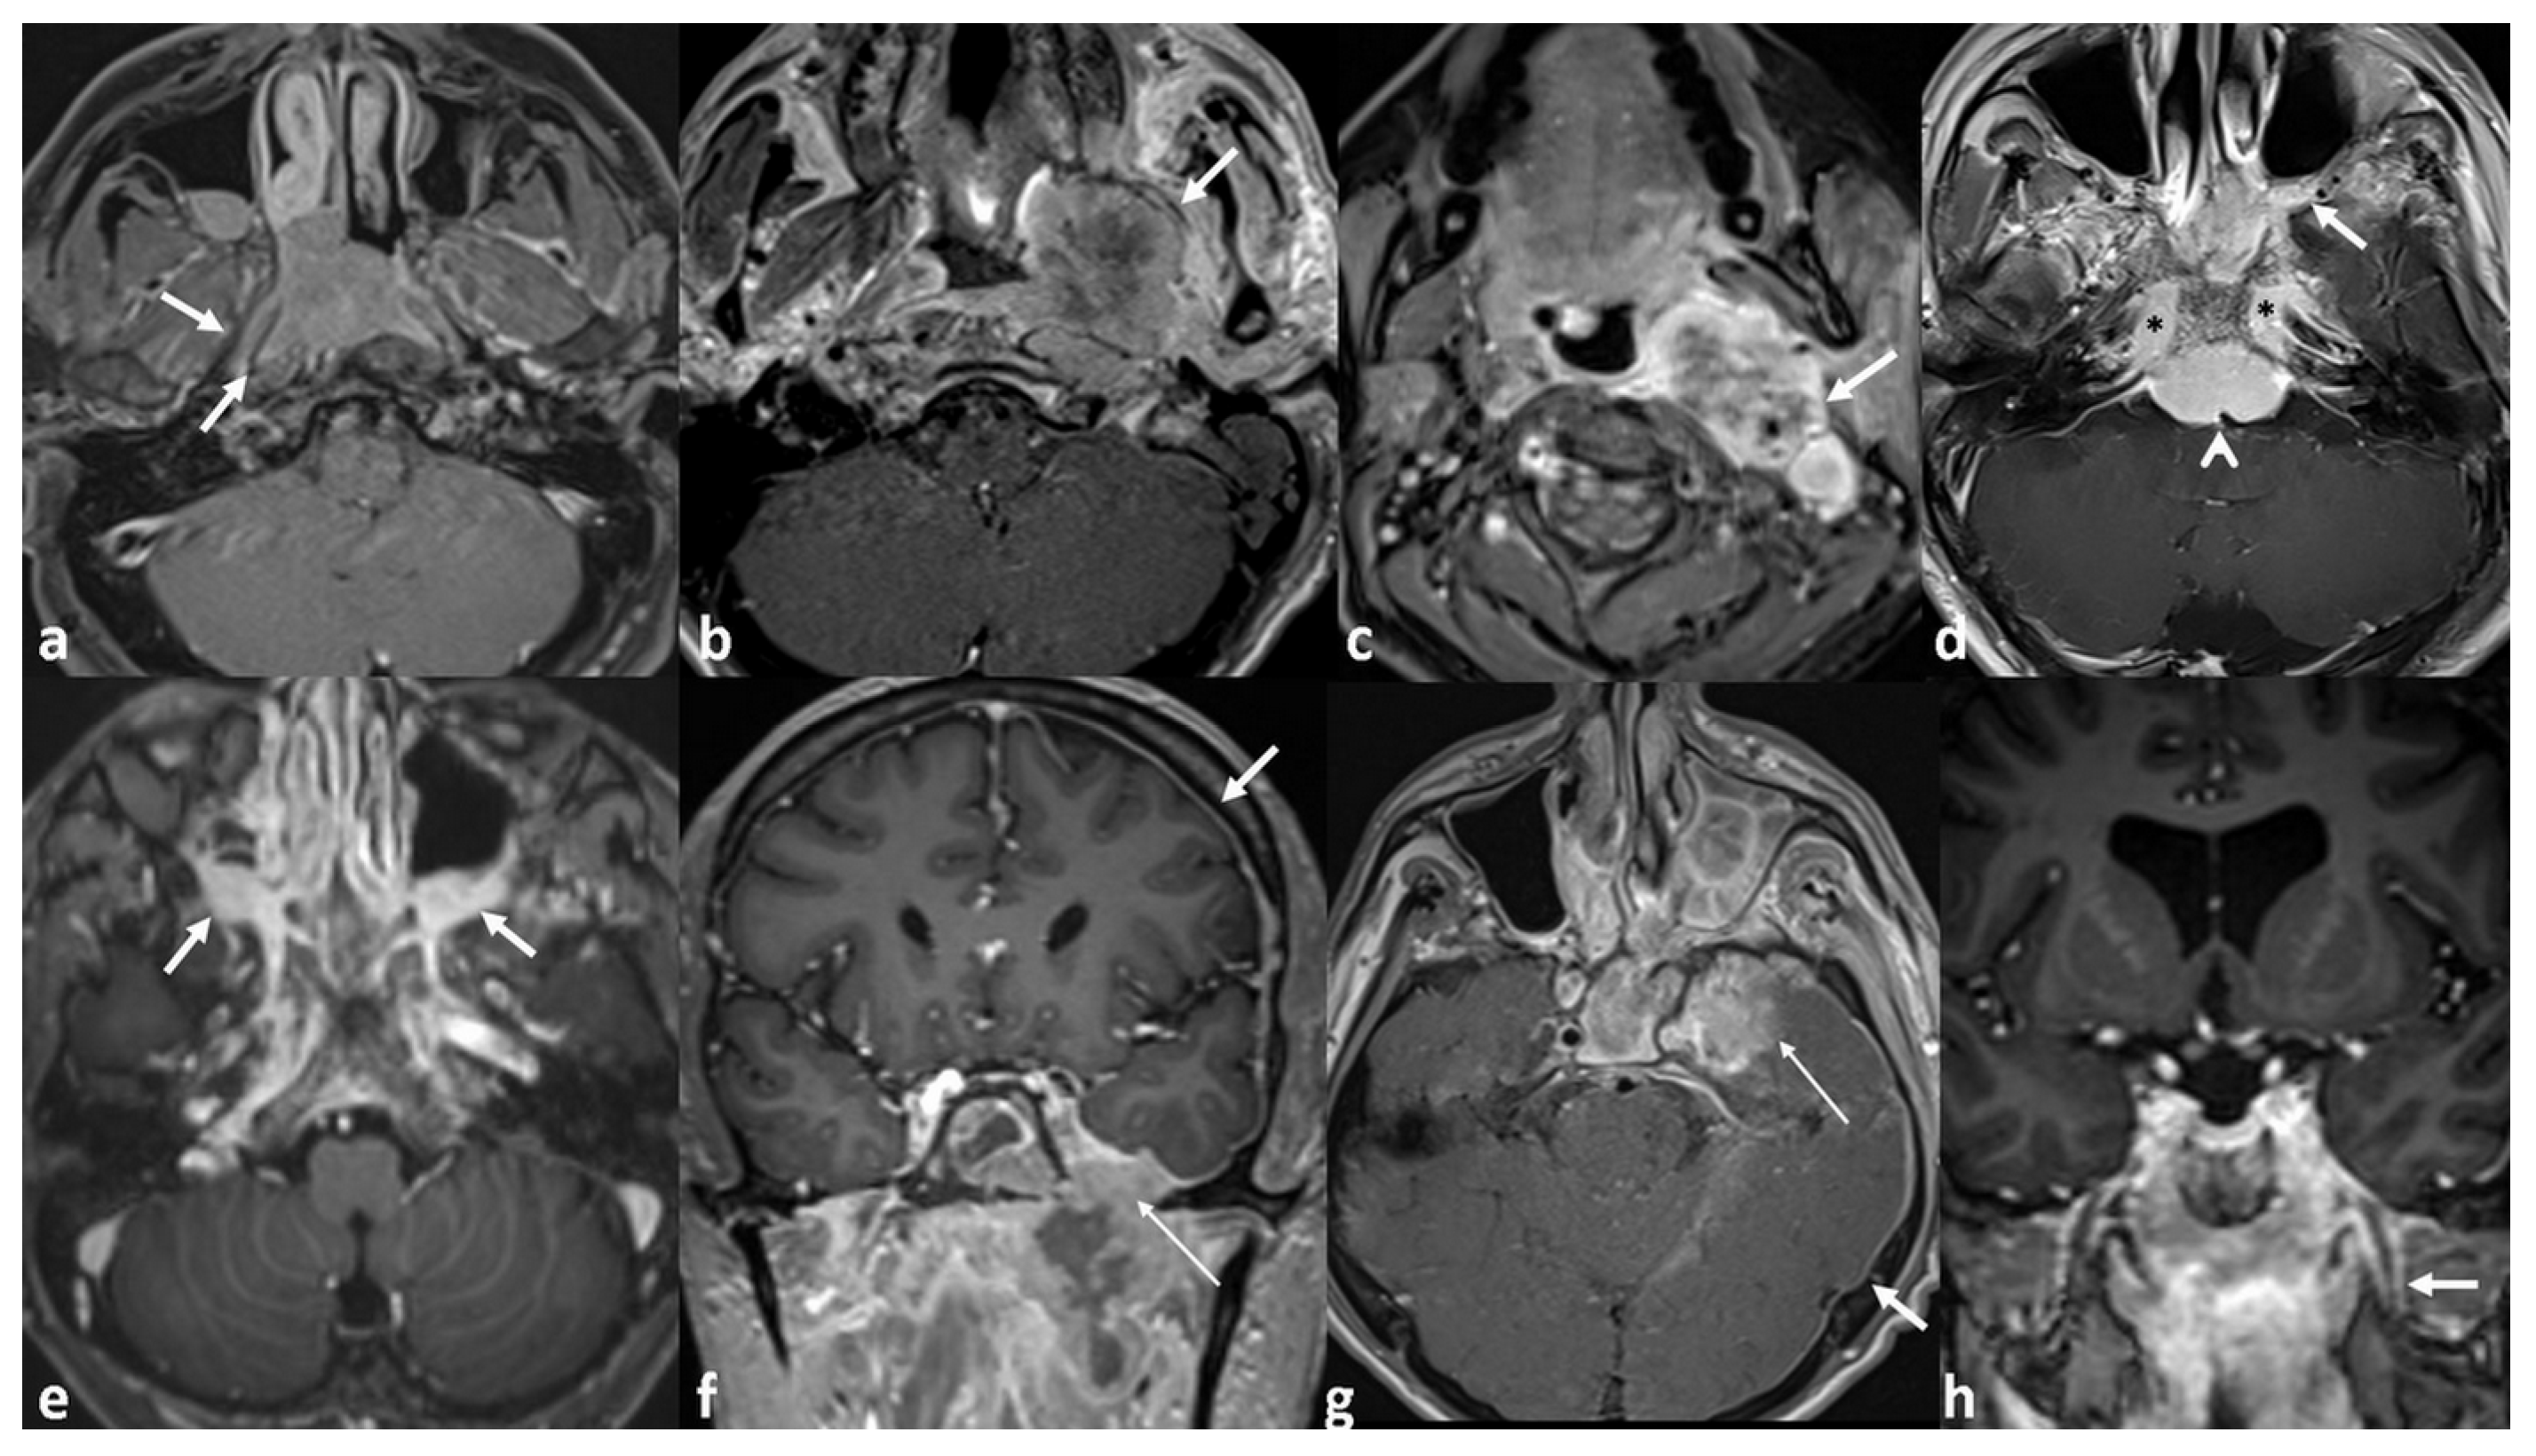

| PT Growth Pattern | 0.014 * | 0.897 | |

| Mass-forming | 9/44 (20.4%) | ||

| Infiltrative | 5/8 (62.5%) | ||

| PPS invasion | 0.001 * | 0.027 * OR: 1.23 95%CI [1.03–1.49] | |

| No | 1/9 (11.1%) | ||

| Local | 3/27 (11.1%) | ||

| Extensive | 10/16 (62.5%) | ||

| ICS invasion | 0.008 * | 0.076 | |

| No | 7/41 (17%) | ||

| Local | 5/8 (62.5%) | ||

| Extensive | 2/3 (66.6%) | ||

| Perineural invasion | <0.001 * | 0.029 * OR: 1.60 95%CI [1.05–2.43] | |

| Positive | 7/43 (16.2%) | ||

| Negative | 7/9 (77.7%) | ||